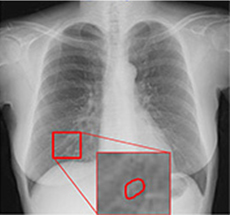

注意:赤枠は実際には表示されません。

Temporal Subtraction処理は、独自のアルゴリズム補正をもとに、胸部画像の現在と過去の差分画像を生成する画像処理技術です。

そこで、現在と過去の差分画像を生成し「変化の有無」を可視化することで、診断精度の向上と時間短縮が期待でき、胸部読影を強力にサポートします。

◆肺門部や心臓裏の見落としやすい部位の病変が見つけやすくなる。

肺門部裏は見落としやすく重要な読影ポイントですが、経時差分画像により一目で変化が確認出来ます。